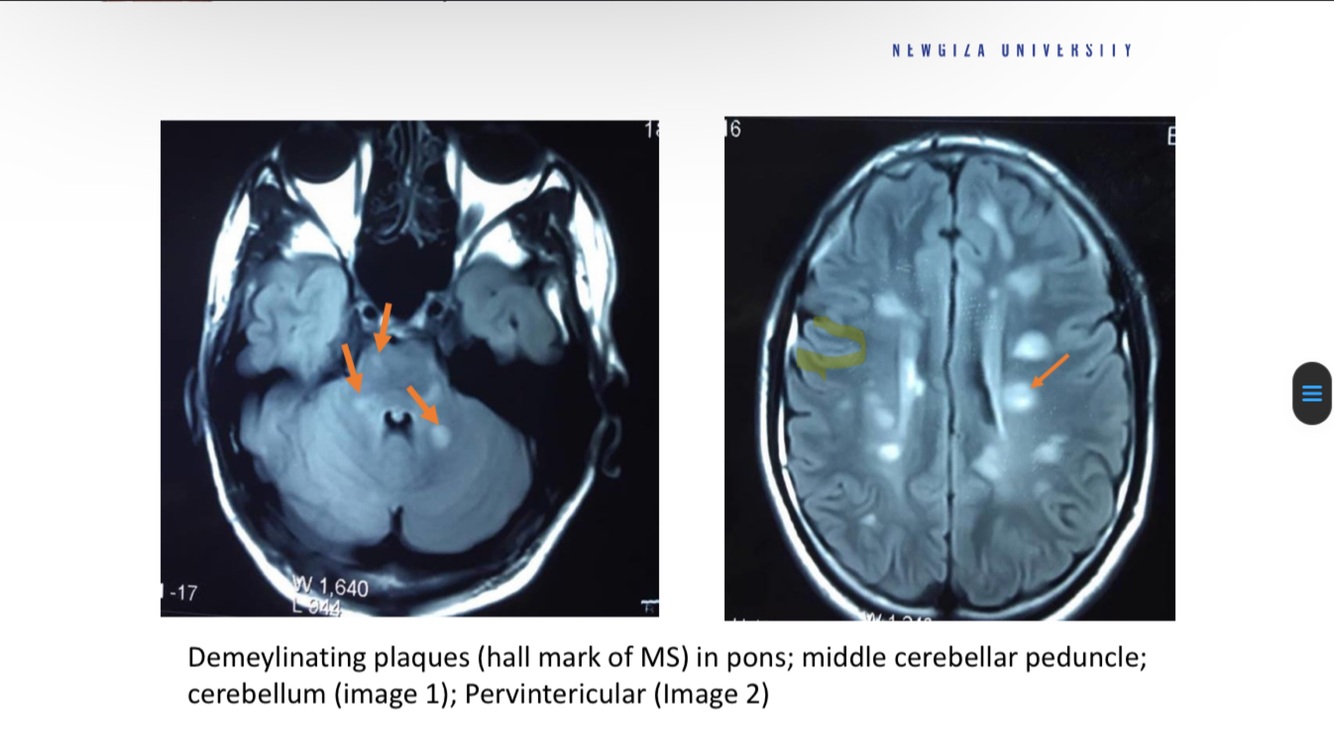

Diagnose

what do you see